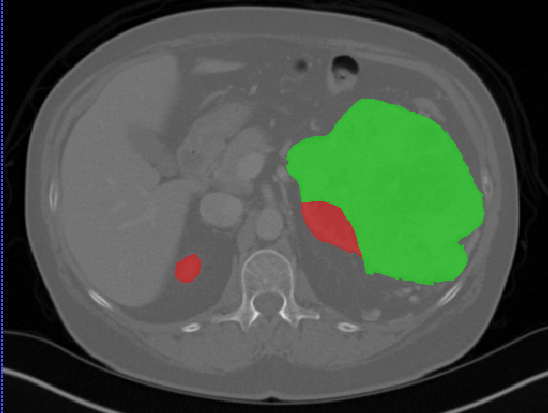

We first introduce a method for connecting the output of a CNN to an ACM, yielding a model for the precise delineation of lesions, to which we refer as Deep Active Lesion Segmentation (DALS) (Figure 4). We then go further to introduce a truly unified framework (Figure 5) that bridges the gap between ACMs and CNNs by leveraging a novel, automatically differentiable level-set ACM with trainable parameters that allows for back-propagation of gradients and can be end-to-end trained along with a backbone CNN from scratch, without any CNN pre-training. The ACM is initialized directly by the CNN and utilizes an energy functional that is locally-tunable by the backbone CNN, through 2D feature maps. Thus, our work overcomes the big hurdle of fully automating the powerful ACM approach to image segmentation. We have applied our proposed framework to the task of building segmentation in aerial images (Figure 6).

Deep Active Lesion Segmentation

[45]: Lesion segmentation is an important problem in computer-assisted diagnosis that remains challenging due to the prevalence of low contrast, irregular boundaries that are unamenable to shape priors. We introduce Deep Active Lesion Segmentation (DALS), a fully automated segmentation framework that leverages the powerful nonlinear feature extraction abilities of FCNs and the precise boundary delineation abilities of ACMs. Our DALS framework benefits from an improved level-set ACM formulation with a per-pixel-parameterized energy functional and a novel multiscale encoder-decoder CNN that learns an initialization probability map along with parameter maps for the ACM. We evaluate our lesion segmentation model on a new Multiorgan Lesion Segmentation (MLS) dataset that contains images of various organs, including brain, liver, and lung, across different imaging modalities—MR and CT. Our results demonstrate favorable performance compared to competing methods, especially for small training datasets. -